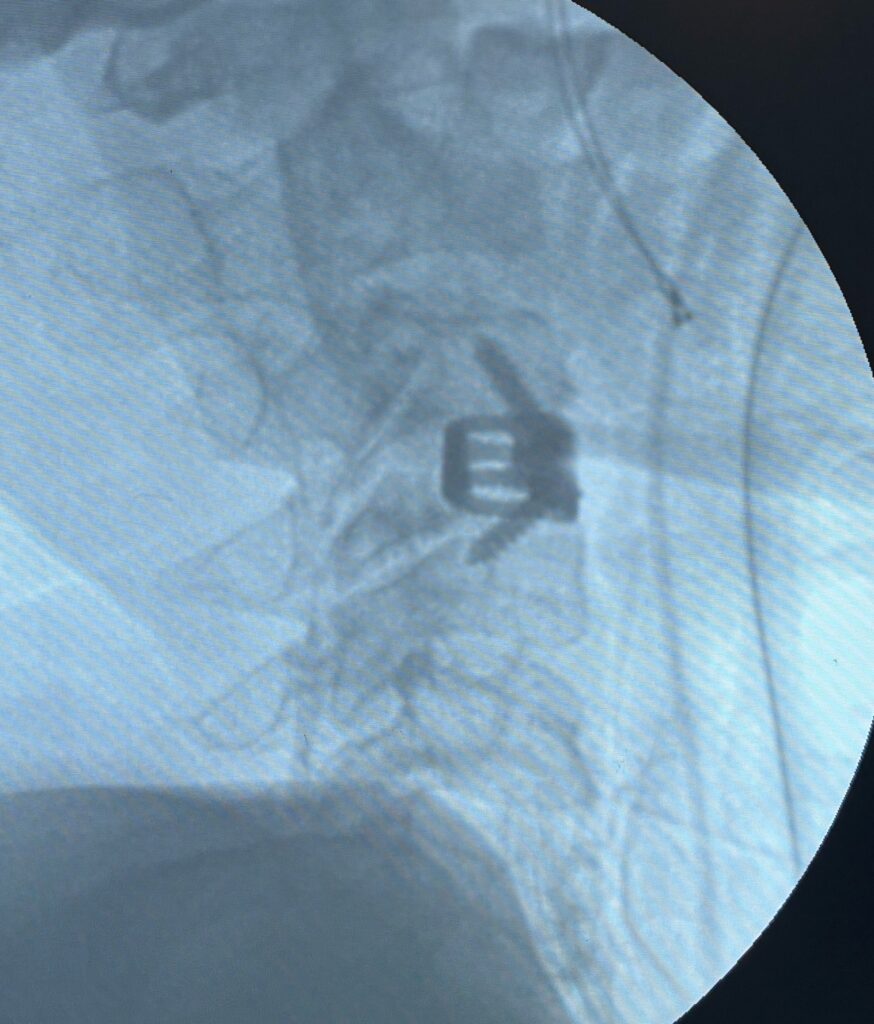

2. Minimally Invasive Procedures

If pain persists, doctors may recommend:

- Steroid injections: To reduce inflammation around nerves

- Nerve block therapy: For pain control and healing support

These procedures are usually safe and allow faster recovery.

Cases treated by Spine Specialist Dr. Gaurav Sandeep Gupta